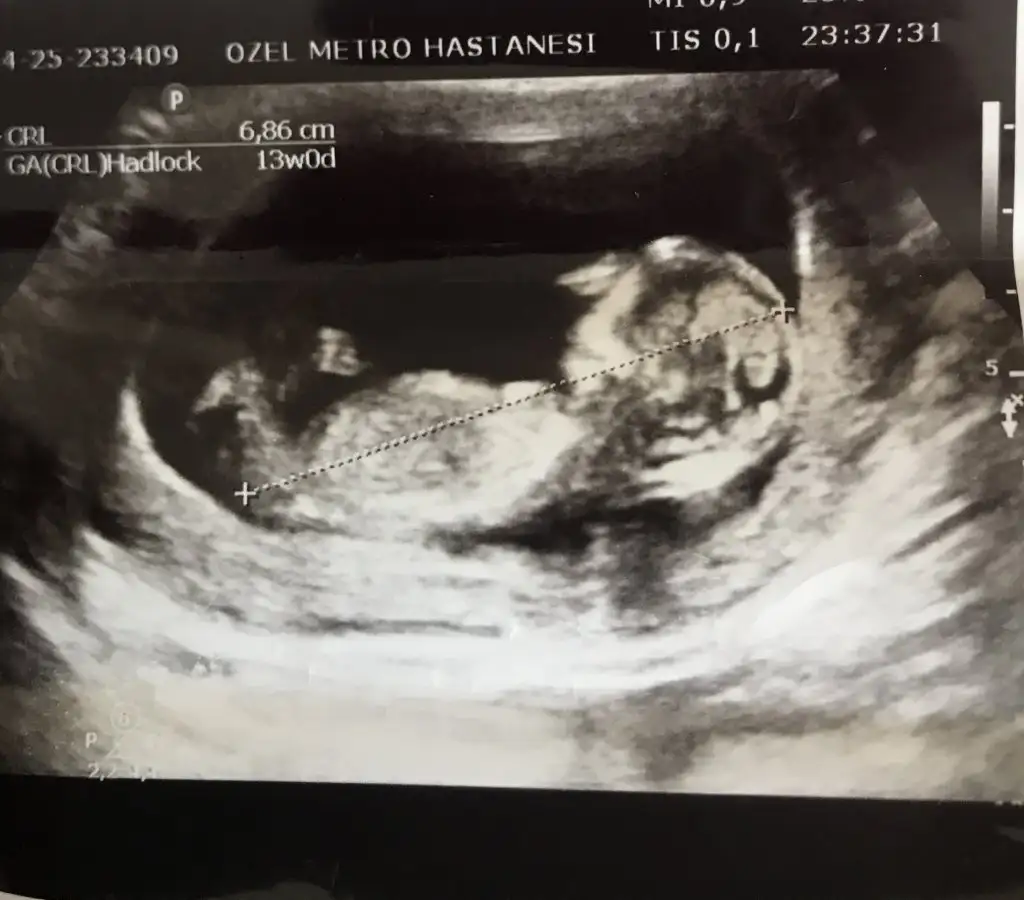

Kız görünüyor13. Hatfta cinsiyet tahmini yapabirmisiniz

Erkek görünüyor gibi en iyi 11 12 13 haftalar olmalıCinsiyet tahmini yapabilirmisiniz 14 haftalik